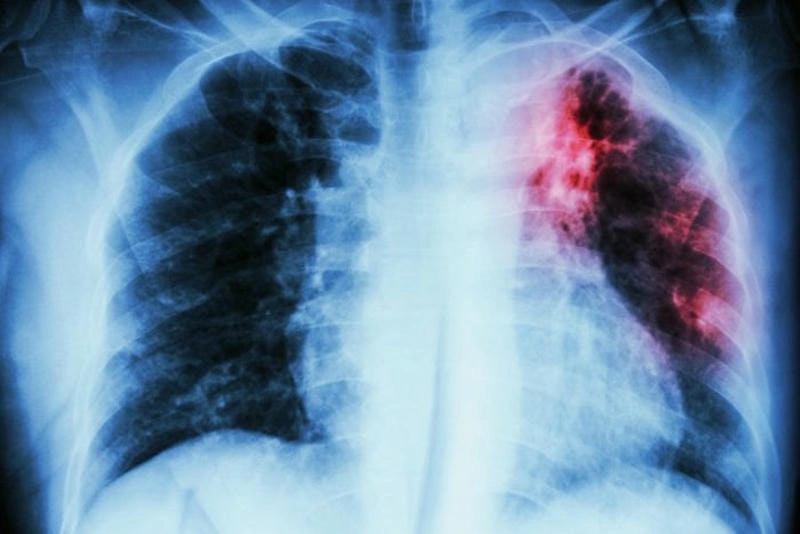

Hình ảnh bệnh lao phổi là tài liệu tham khảo quan trọng giúp người bệnh và bác sĩ dễ dàng nhận biết dấu hiệu bất thường. Việc quan sát hình ảnh X-quang, CT phổi giúp chẩn đoán chính xác mức độ tổn thương và đưa ra phương án điều trị kịp thời.

Bạn sẽ phải rùng mình khi chiêm ngưỡng hình ảnh bệnh lao phổi là như thế nào dưới ống kính y học thực tế. Những bức ảnh chụp X-quang cho thấy phổi bị tổn thương nặng, xuất hiện những đốm trắng mờ như bóng ma ám ảnh. Không chỉ là các tổn thương vật lý, đây còn là những “chứng tích sống” của căn bệnh âm thầm hủy hoại cơ thể qua từng hơi thở. Từ viêm nhẹ đến tổn thương lan rộng, hình ảnh bệnh lao phổi khiến người xem không thể rời mắt vì mức độ nghiêm trọng mà nó thể hiện rõ ràng qua từng chi tiết.

Cảnh báo: tổng hợp ảnh bệnh lao phổi chân thực này không dành cho người yếu tim. Đây là loạt hình ảnh y khoa được các chuyên gia sưu tầm và xác thực, ghi lại quá trình tiến triển của bệnh từ giai đoạn đầu đến giai đoạn nguy kịch. Từng mảng mô phổi bị ăn mòn, xơ hóa, hoại tử được phơi bày rõ nét dưới ánh sáng X-quang lạnh lùng. Những hình ảnh này không chỉ mang tính chất minh họa y học, mà còn là hồi chuông cảnh tỉnh cho bất kỳ ai còn lơ là với căn bệnh nguy hiểm này.